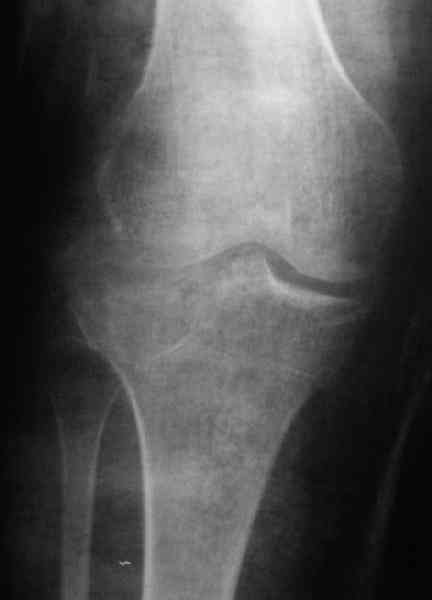

По тактике лечения, более импонирует второй вариант, но наружная плато расколота и туда при нагрузке внедряется н/мышелка бедра, поэтому после дистракции как репонирвать: или стяжными винтами, или изогнутами спицами или субхондральная костная пластика?

Уважаемый Абдурашид. Если нет противопоказаний , то из оперативных способов, я бы рекомендовал следующие: Полное замещение наружного мыщелка аллотрансплантатом либо открытая репозиция с элевацией и замещение дефекта ауто или аллокостью. В Ваших условиях , я бы рекомендовал второй способ. Во-время элевации необходимо разъединить фрагменты со стороны сустава ( надсечь скальпелем по линиям перелома, а затем тонким остеотомом их разъединить. При помощи долота произвести неполную остеотомию ( захватите не менее 1,5 - 2 см губчатой кости и поднять фрагменты, визуально отрепонировать и фиксировать 2-3 спицами. Дефект заместить костным ауто или аллатрансплантатом. Окончательная стабилизация пластиной ( лучше с угловой стабильностью, либо АВФ - позволит спокойно устранить угловую деформацию.

Недавно поступила больная через 1,5- 2 месяца.